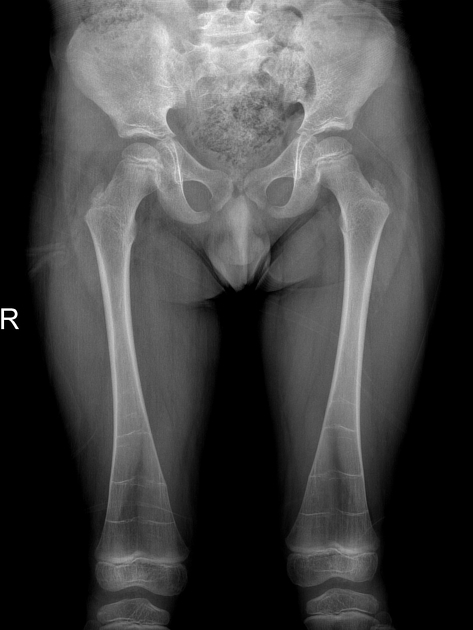

What is metaphyseal flaring/Erlenmeyer flask deformity? LEAD Gnome (gnome storing calcified blood)

1. Anaemias (thalassaemia, sickle cell anemia, pure red cell aplasia)

fibrous dysplasia

2. Storage diseases (Gaucher disease , Niemann-Pick disease)

3. Bone dysplasias: fibrous dysplasia, multiple osteochondromatosis, enchondromatosis amongst many others

4. Osteopetrosis